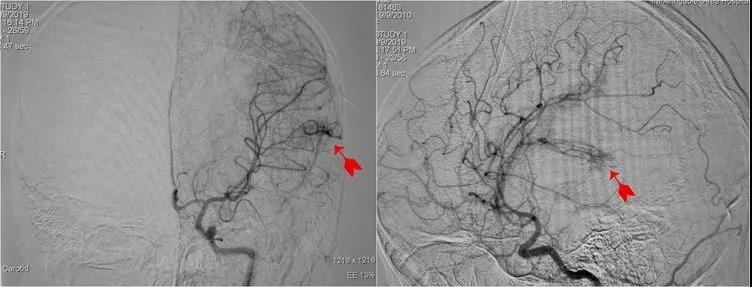

↑DSA检查

果不其然,DSA结果显示:左颞动静脉血管畸形团约2x2cm,由大脑中动脉下干M4远端供血引流静脉发育不完全。